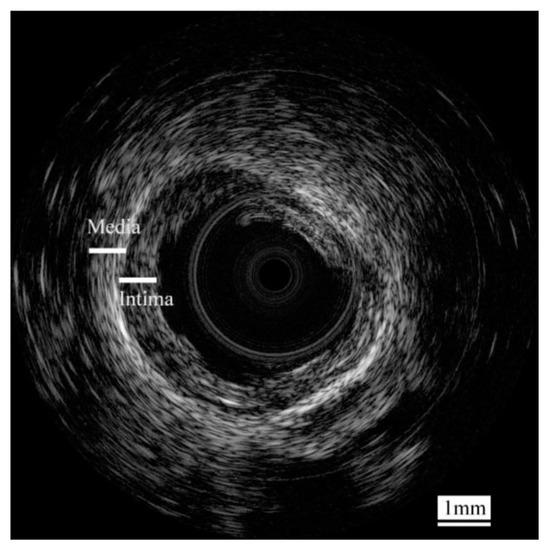

- Yan, X.; Lam, K.H.; Li, X.; Chen, R.; Ren, W.; Ren, X.; Zhou, Q.; Shung, K.K. Correspondence: Lead-free intravascular ultrasound transducer using 0.5BZT–0.5BCT ceramics. IEEE Trans. Ultrason. Ferroelectr. Freq. Control 2013, 60, 1272–1276. [Google Scholar] [CrossRef] [PubMed]